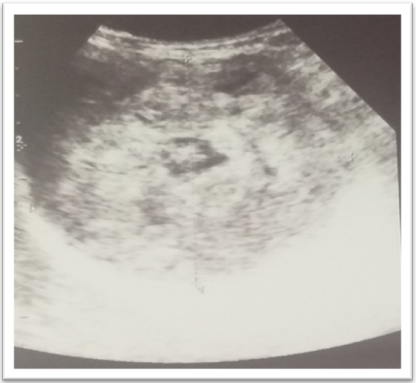

On mammary ultrasound: two well-limited, rounded masses with discreetly irregular contours, hypoechoic and heterogeneous, the larger one with a few central cystic cubicles measuring 88 x84 x81 mm in the upper inner quadrant of the right breast and the other lesion in the right lower inner quadrant measuring 39 x37 x35 mm (figure 3). The two lesions were classified as BIRADs 4.

Figure 3. Ultrasonographic Appearance of The Mass.